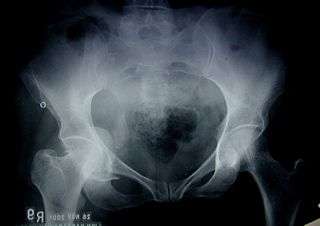

Fractures of the acetabulum occur when the head of the femur is driven into the pelvis. This is caused either by a blow on the side or by a blow in the front of the knee, usually in a dashboard injury when the femur also may be fractured.[1]

To understand fracture pattern it is essential to have minimum three x-ray views;

- · Pelvis with both hips antero posterior view

This view shows six important landmarks of the acetabulum, viz;